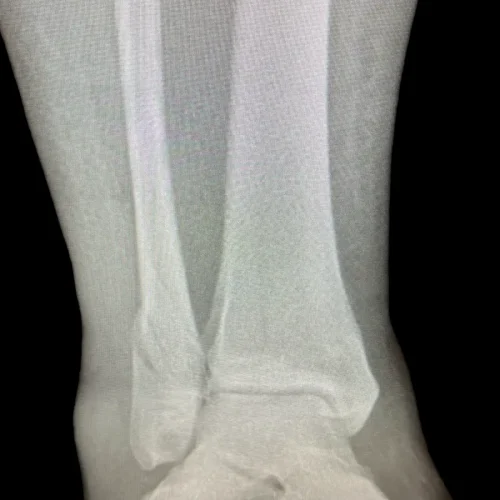

Surgical Intervention at Stepwell Institute is never a “one-size-fits-all” solution. We view surgery as a precise tool used to restore the natural biomechanics of the foot and ankle when non-invasive methods have reached their limit. Our philosophy centers on individualized surgical planning—using advanced imaging to map out the procedure before you ever enter the operating room. From correcting bunions and hammertoes to performing ligament repairs and fracture fixations, Dr. Yakov utilizes techniques designed to minimize trauma to the surrounding tissues, thereby reducing the risk of complications and ensuring a more stable, long-term result for our patients.

Stepwell Institute distinguishes itself by offering NJ patients access to the most advanced surgical modalities in modern podiatry. We specialize in Surgical Intervention, which utilize smaller incisions and specialized instruments to reduce post-operative pain and scarring. For more complex cases, we employ 3D-printed surgical guides and biological grafts to enhance the body’s natural healing ability. By choosing Stepwell Institute, you benefit from a specialized recovery plan where Dr. Yakov and our team prioritize early, safe mobilization. Our goal is to provide a definitive surgical solution that allows you to return to the active New Jersey lifestyle you love with confidence and strength. confidence and strength.

Our Case Study